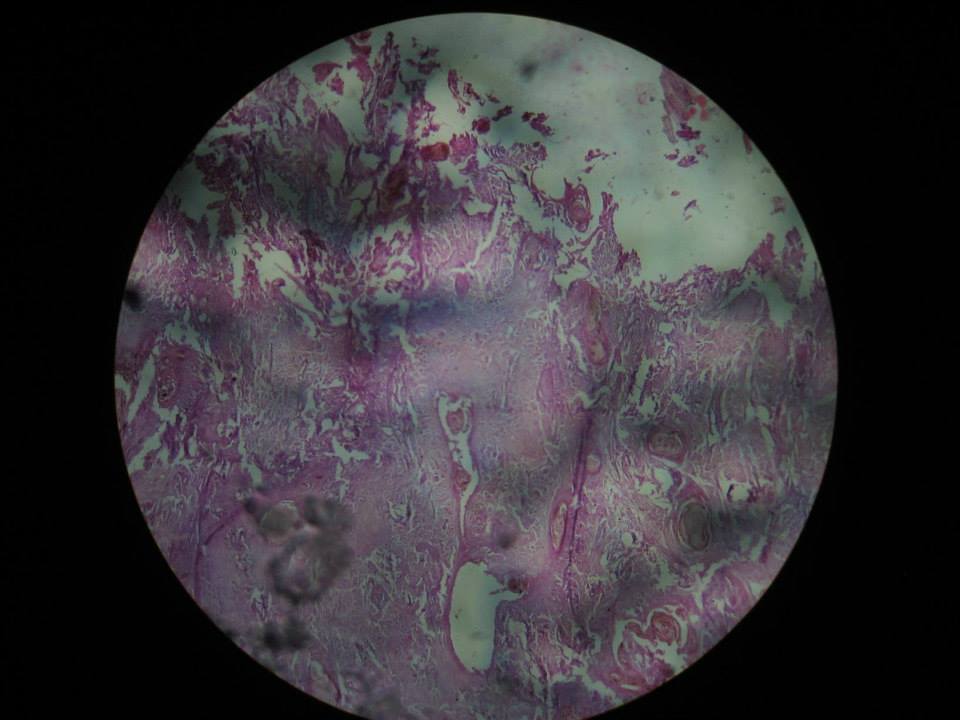

4th Year Pathology Slides and Models Kemcaana CD

Download the following files then practice the images given below